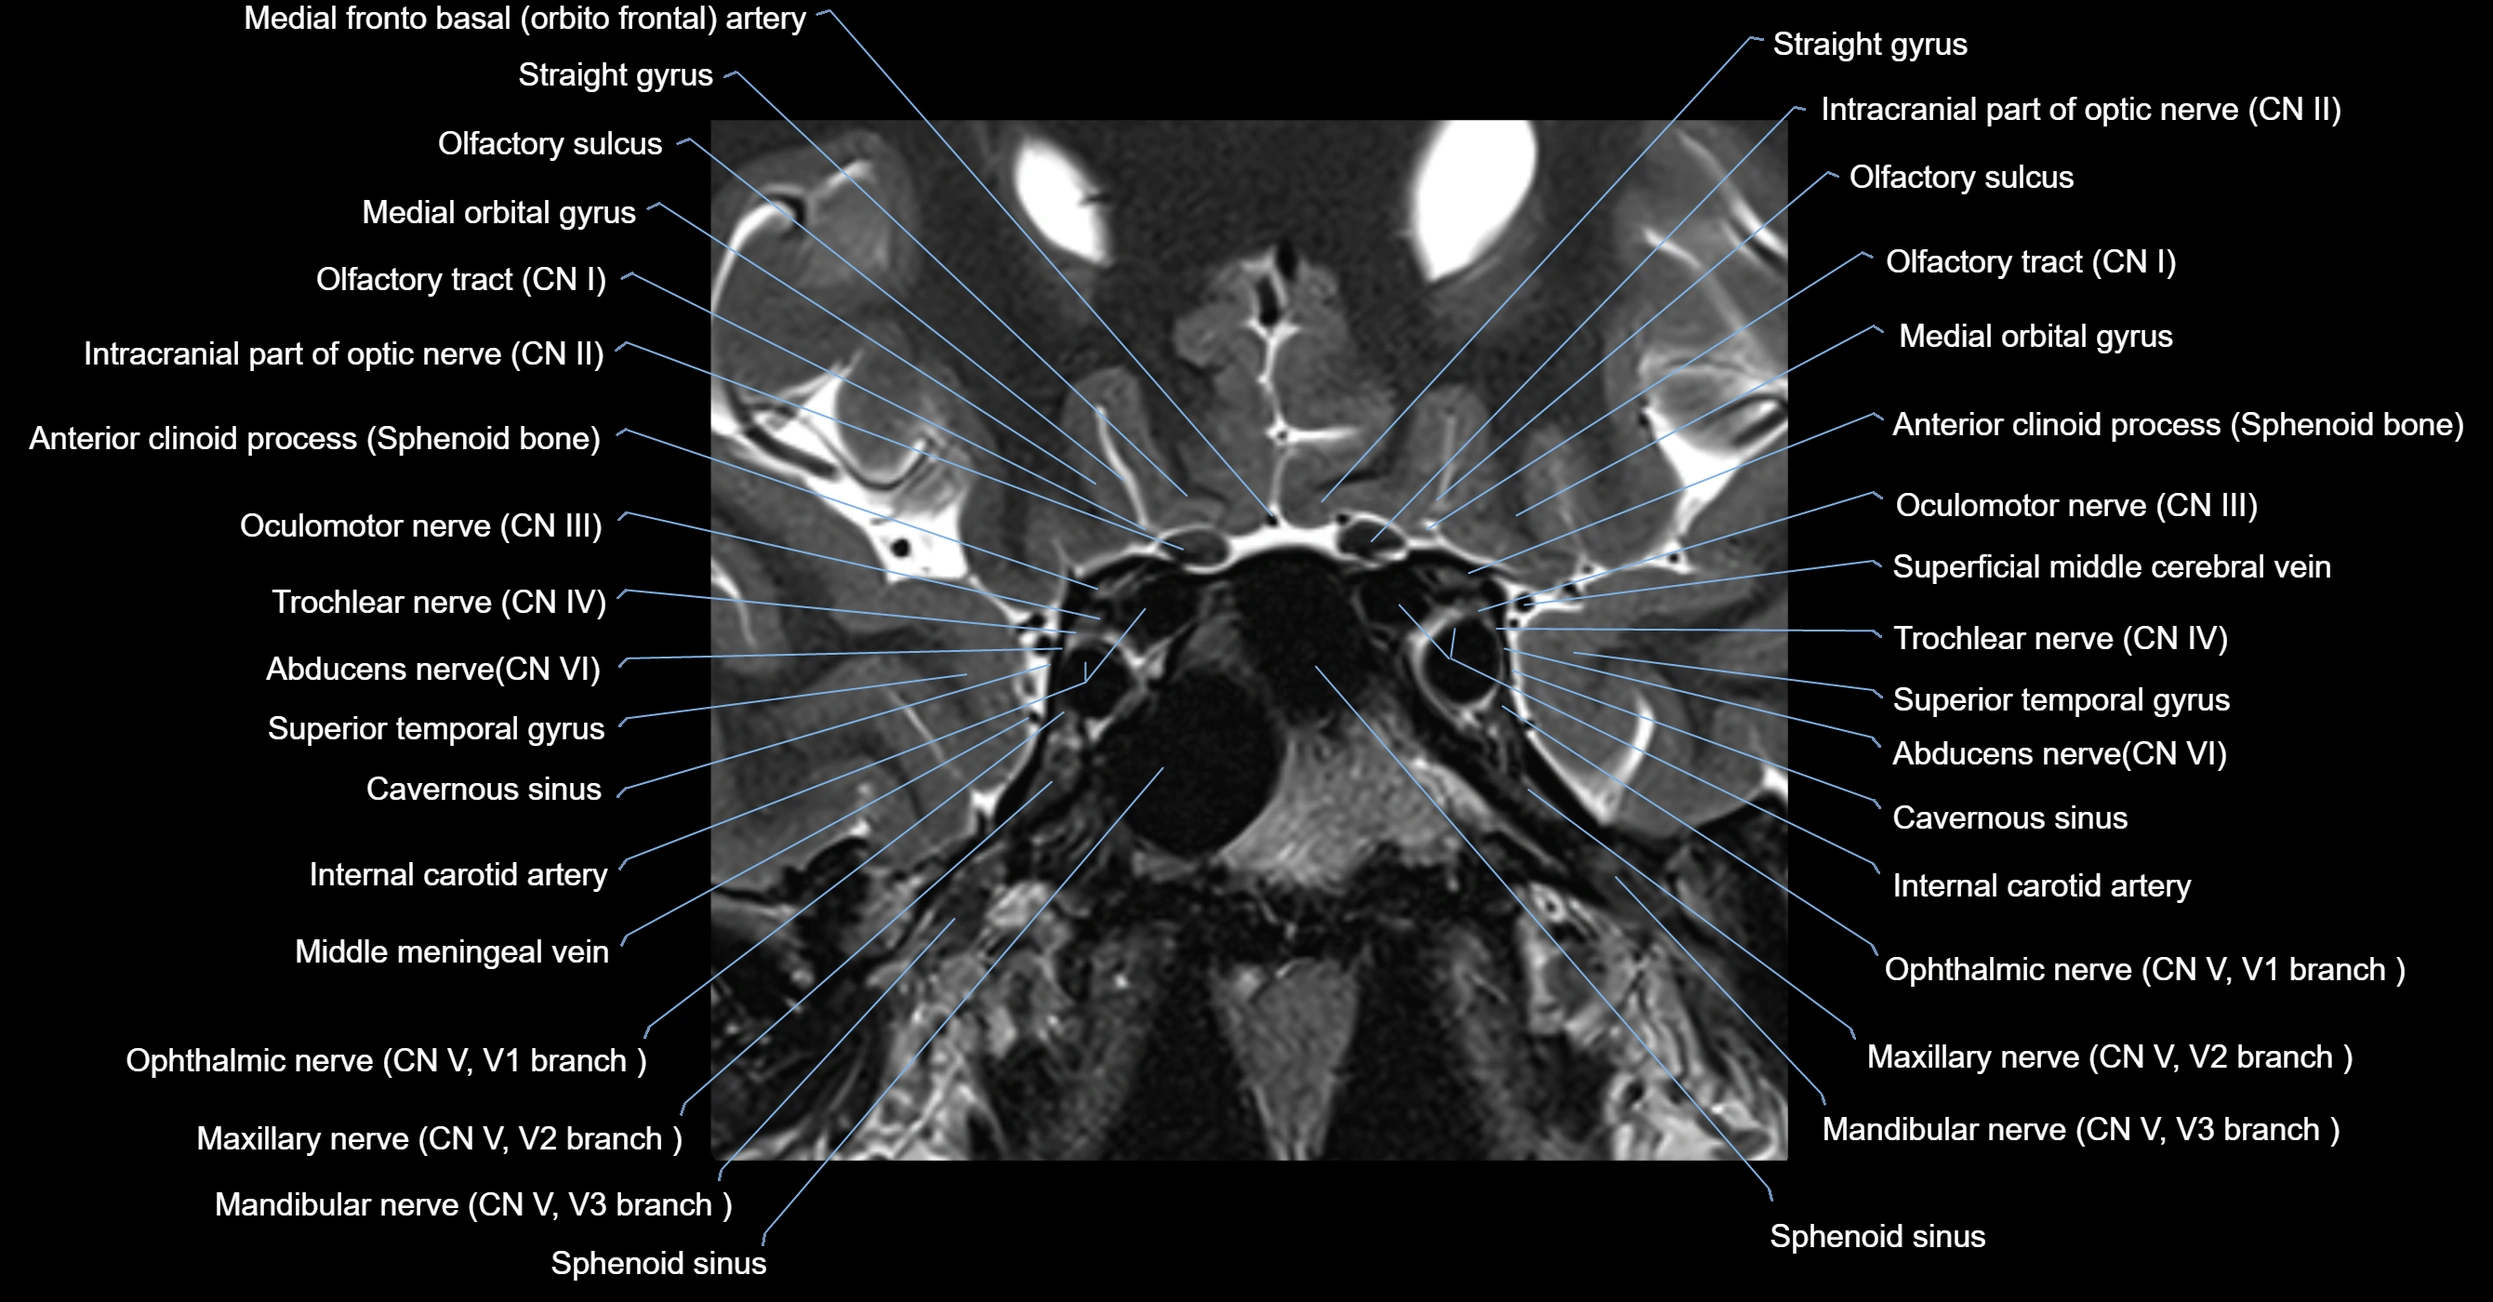

MRI images